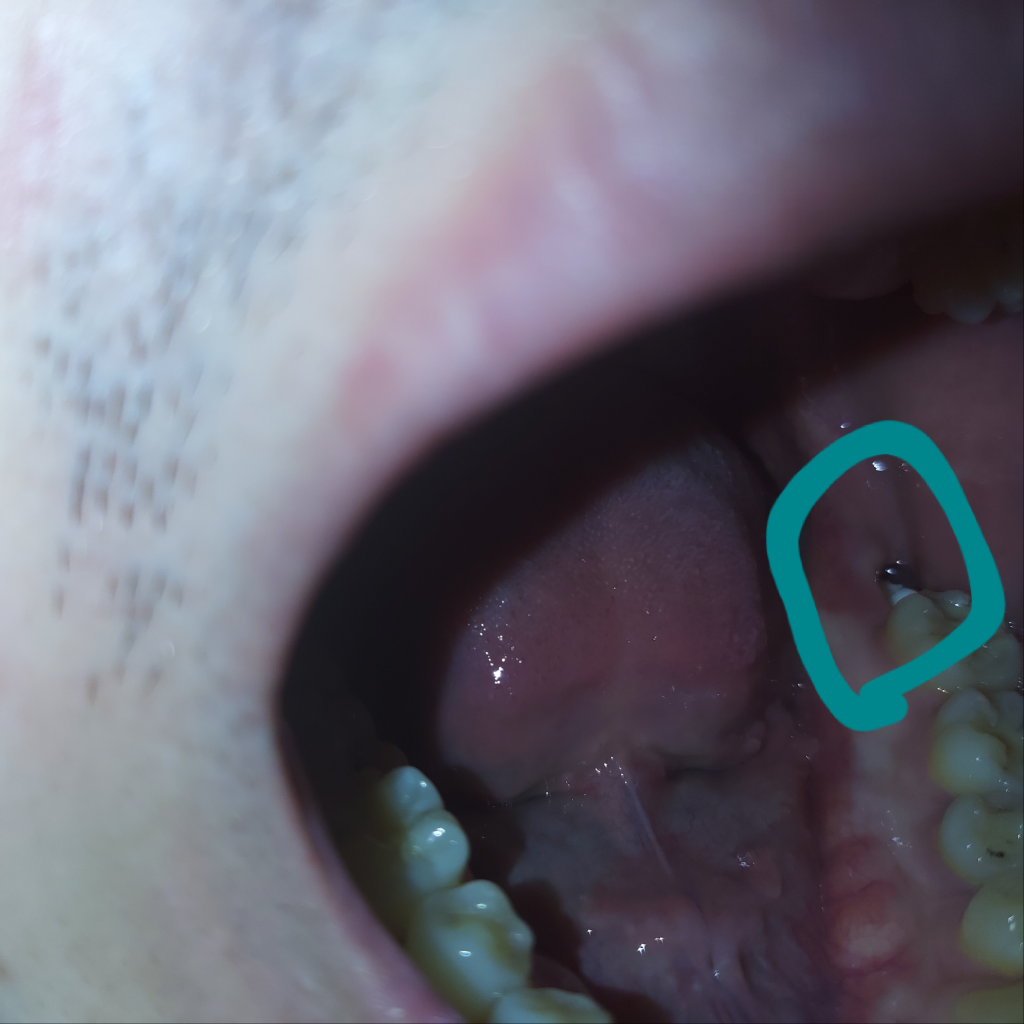

그리고 두번째 사진은 이에서 떨어져ㅜ나온 물질입니다.

• 2번 째 사진